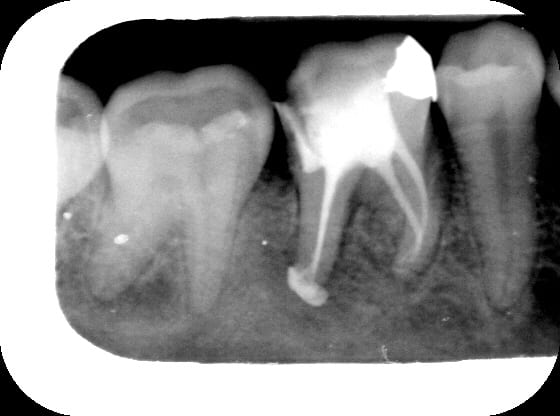

bon, voici un cas tout neuf...hervé, abces endo paro.. vu en urgence le 1er mars....ttt: ouverture+h2o2/laser ds poche.... voici les photos à J0 et J5 + rx de l' endo laser du J5...(petit delta racine distale)...

les rx: